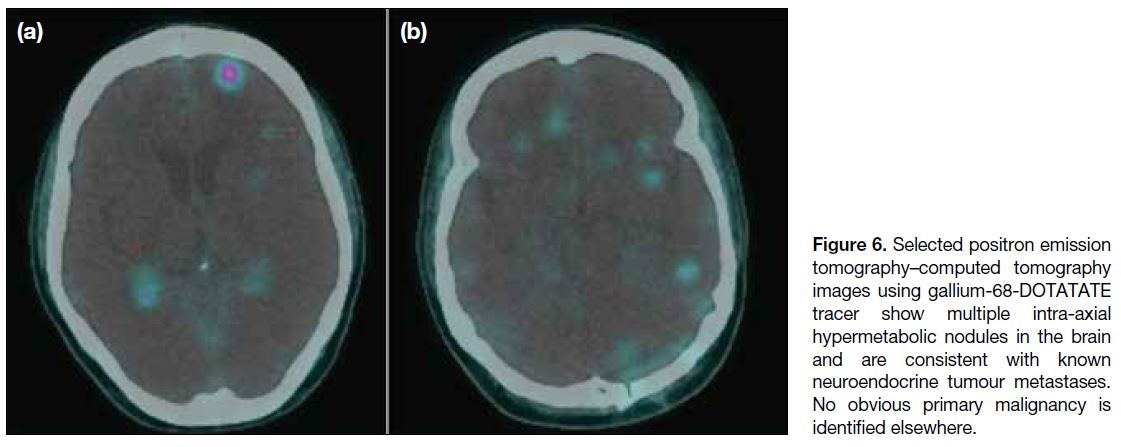

a metastatic lesion was likely. A repeated whole-body

PET-CT with gallium-68-DOTA-tyr3-octreotate (Ga-68-DOTATATE) showed multiple hypermetabolic nodules

in the brain suggestive of known neuroendocrine tumour

(Figure 6), but still no obvious location for a primary

malignancy. A preliminary diagnosis was reached of

neuroendocrine tumour of unknown origin, with possible

Figure 6. Selected positron emission

tomography–computed tomography

images using gallium-68-DOTATATE

tracer show multiple intra-axial

hypermetabolic nodules in the brain

and are consistent with known

neuroendocrine tumour metastases.

No obvious primary malignancy is

identified elsewhere.